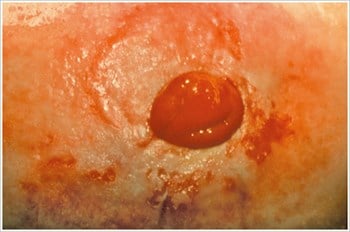

Pyoderma Gangrenosum3

Description/causes : Une maladie inflammatoire de la peau souvent observée chez les patients atteints d’une maladie inflammatoire de l’intestin (MII) telle que la maladie de Crohn ou la colite ulcéreuse.

Symptômes : Ulcères irréguliers, rouges, douloureux, infectés, avec des marges roulées rouges à violettes ; apparaissent sur les jambes, les fesses, le visage et la région péristomiale.